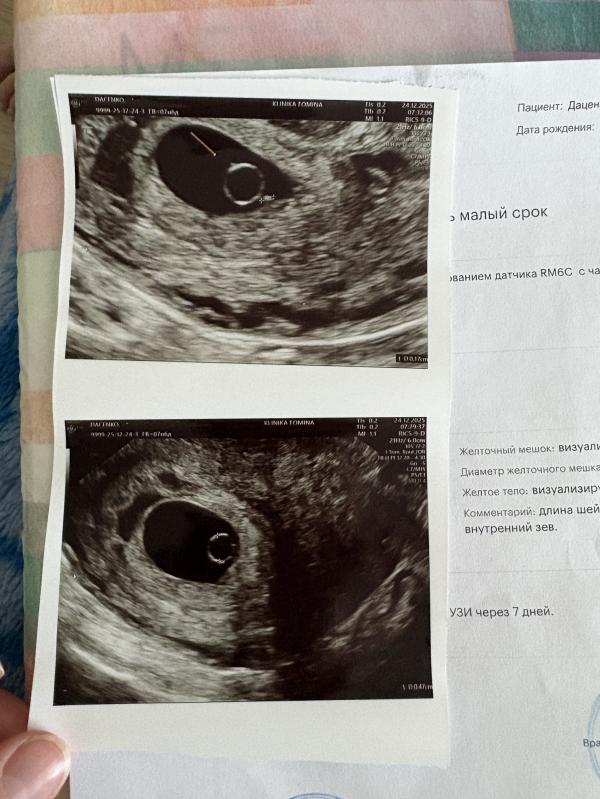

В субботу была на узи нашли пя 14мм и желточный мешочек 3,3мм срок по м 7,2 недели, но у меня была поздняя овуляция на 18-19 день цикла. Накрутила себе все самое страшное из-за первого узи в другой клинике где ничего не соответствовало. Не выдержала неделю пошла сегодня переделать чтобы у покоиться немного. Вот нашли пя уже 16,5мм, жм 4,7мм и маленькую точечку 1,7мм. Очень надеюсь эта точечка за неделю вырастет и превратится в прекрасного эмбриона с сердцебиением. После замершей беременности в и...